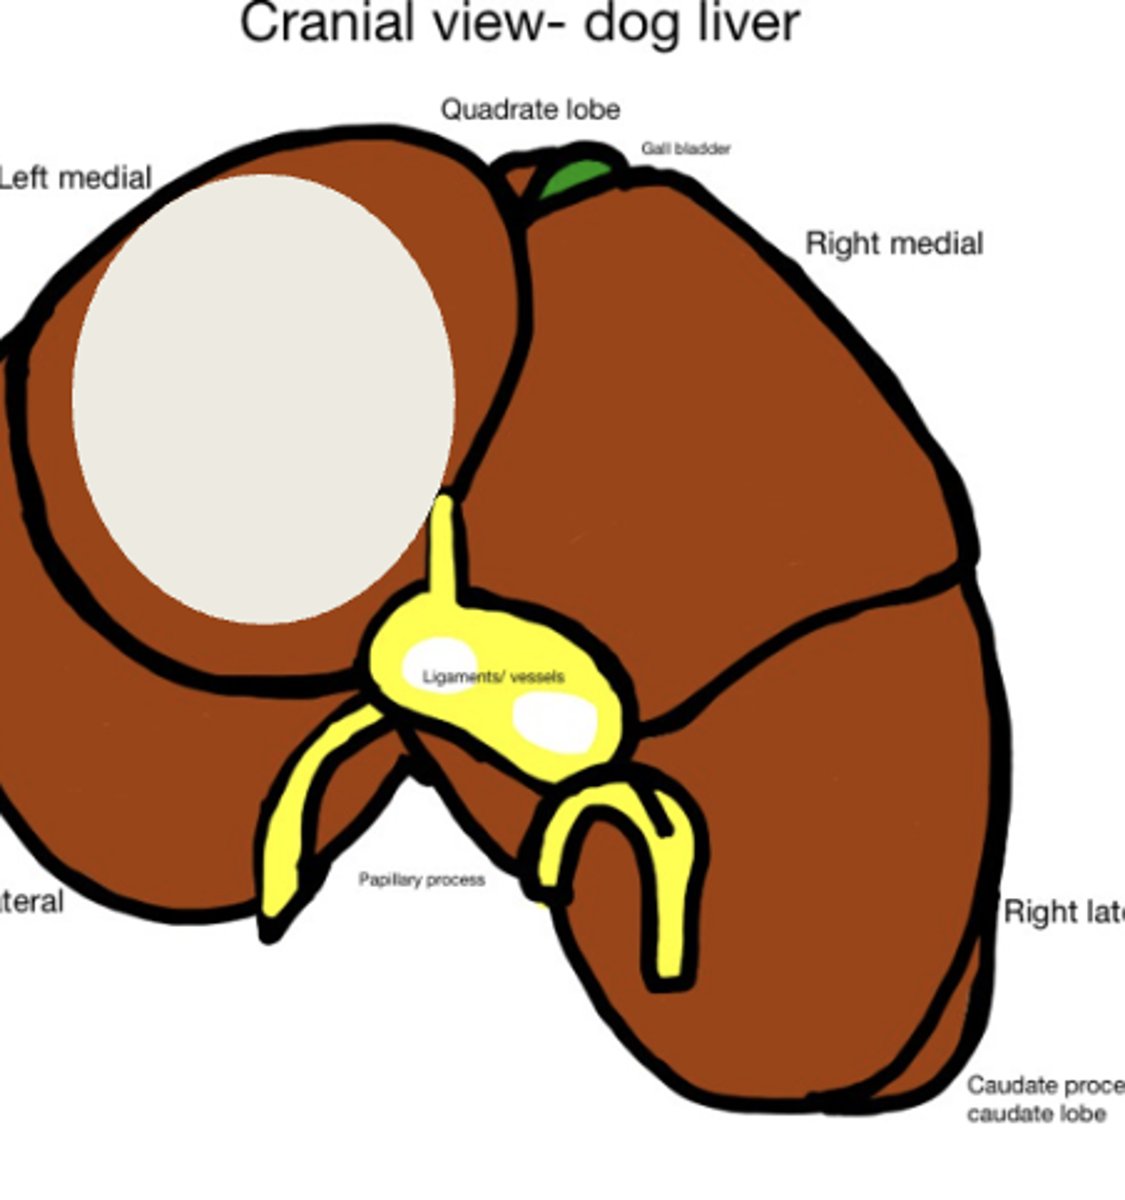

Cirrhosis caused by long term exposure to toxic substances

What has caused this gross appearance of this dog liver